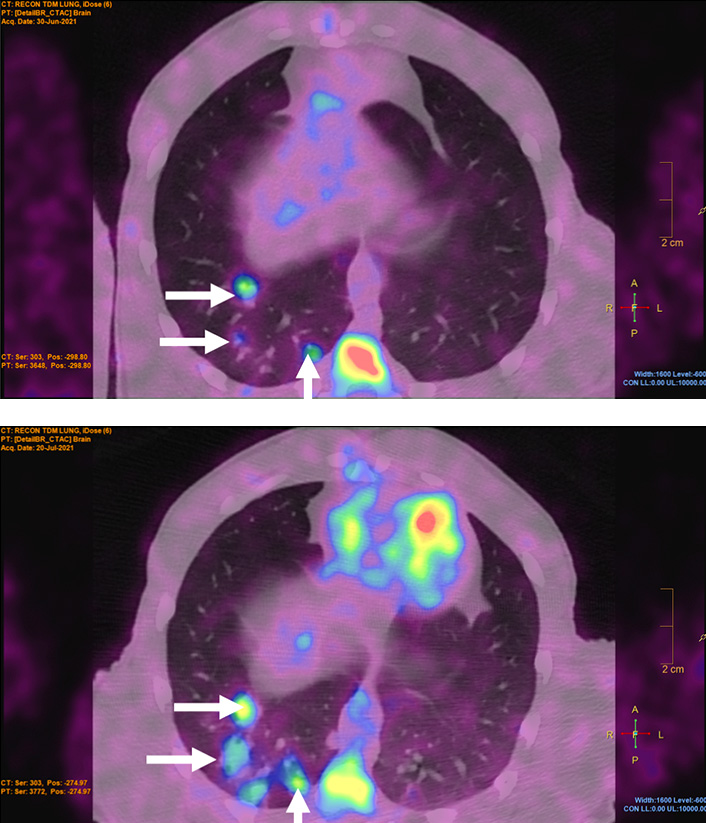

Les chercheurs d’IDMIT développent un modèle d’étude animal d'infection par le pathogène responsable de la tuberculose, destiné à reproduire fidèlement la pathologie humaine. La maladie, la réponse immunitaire et les mécanismes mis en jeu sont caractérisés par l’analyse approfondie de différents échantillons et suivis par imagerie in vivo dans l'organisme entier.